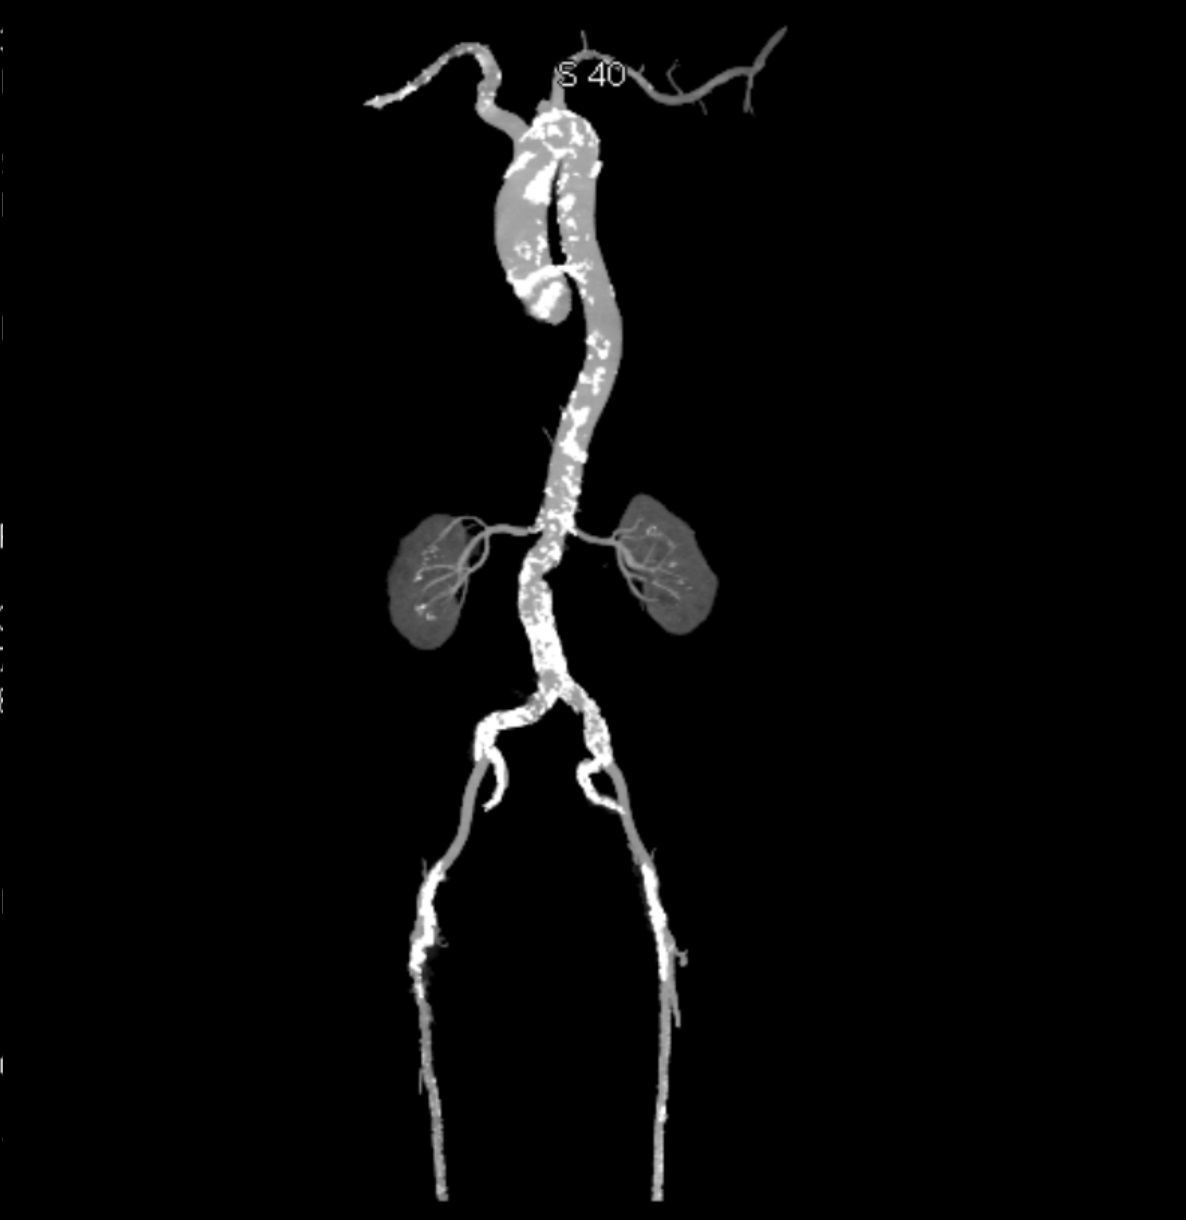

Echocardiography confirmed severe aortic stenosis with a tricuspid aortic valve (aortic valve area 0.9 cm², peak gradient 42 mmHg, mean gradient 25 mmHg) and mildly reduced left ventricular function (LVEF 45%). CT angiography demonstrated extensive calcification of the thoracic and abdominal aorta, severe stenosis of the right superficial femoral artery, and significant stenosis at the ostia of both renal arteries. The aortic valve showed severe calcification, with an Agatston score of 3017.